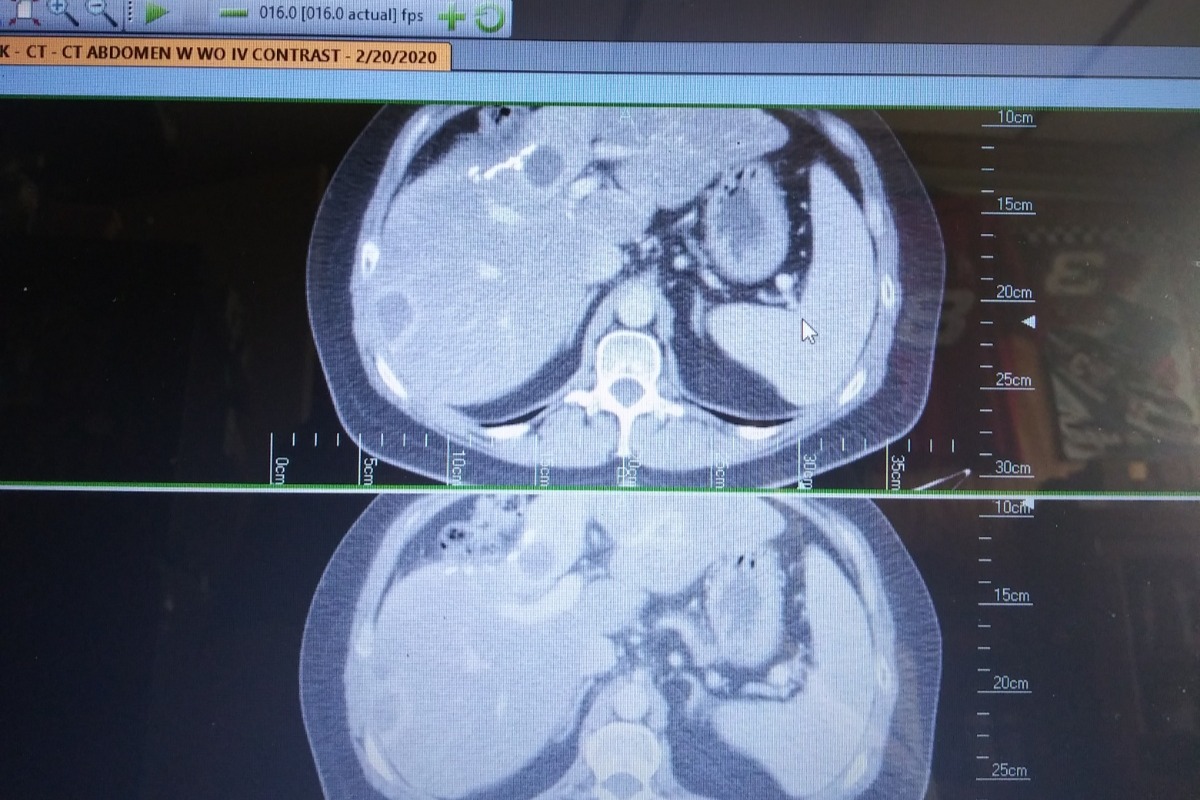

Last February I was diagnosed with Cholangiocarcinoma. This is a rare cancer of the liver bile ducts and will never go away . Abruptly, the company I worked for (AT HOME) decided to terminate me without notice and I lost my health insurance. In order for me to continue my Chemotherapy I have to go through Cobra which is not cheap. Unfortunately my husband just changed jobs and the insurance does not start until May 1st. I do not qualify for anything else so this is my only route. Attached are some pictures from todays CT scan.